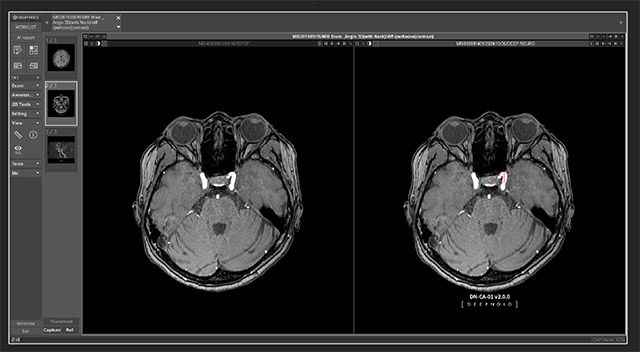

딥노이드가 개발한 M4CXR은 흉부 X-ray 영상을 분석해 판독문 초안을 생성하는 거대 언어 모델(LLM)로 설계된 클라우드 기반의 의료 AI 솔루션이다.

딥노이드는 이번 모델에 그동안 쌓아온 노하우를 반영해 흉부(Chest)에 특화한 도메인과 데이터 구성을 적용했으며, ChatGPT와는 기능적인 차이가 있다고 전했다. 또한, M4CXR는 다양한 각도의 x-ray 영상을 고려해 판독을 진행하고, 기존 영상과 비교해서 추적관찰 가능한 판독문을 생성하는 등 흉부 x-ray 판독에 최적화한 기능을 갖췄다.